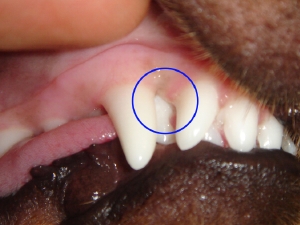

● 上顎乳歯犬歯が抜けなかったことによる不整咬合

乳歯犬歯が抜けなかったことにより、永久歯犬歯が前方に移動し(より鼻先の方向)下顎の犬歯により永久歯犬歯が外側に持ち上げられてしまっています。

緑:上顎永久歯犬歯。適正な場所よりも前方かつ外側にある

青:上顎乳歯犬歯。本来は抜けているべきであるが、抜けていないために、永久歯犬歯(緑)を異常な場所に圧迫している。

赤:下顎永久歯犬歯。正常な位置よりも内側かつ前方にずれている。また上顎の永久歯犬歯(緑)を下から押し上げている。